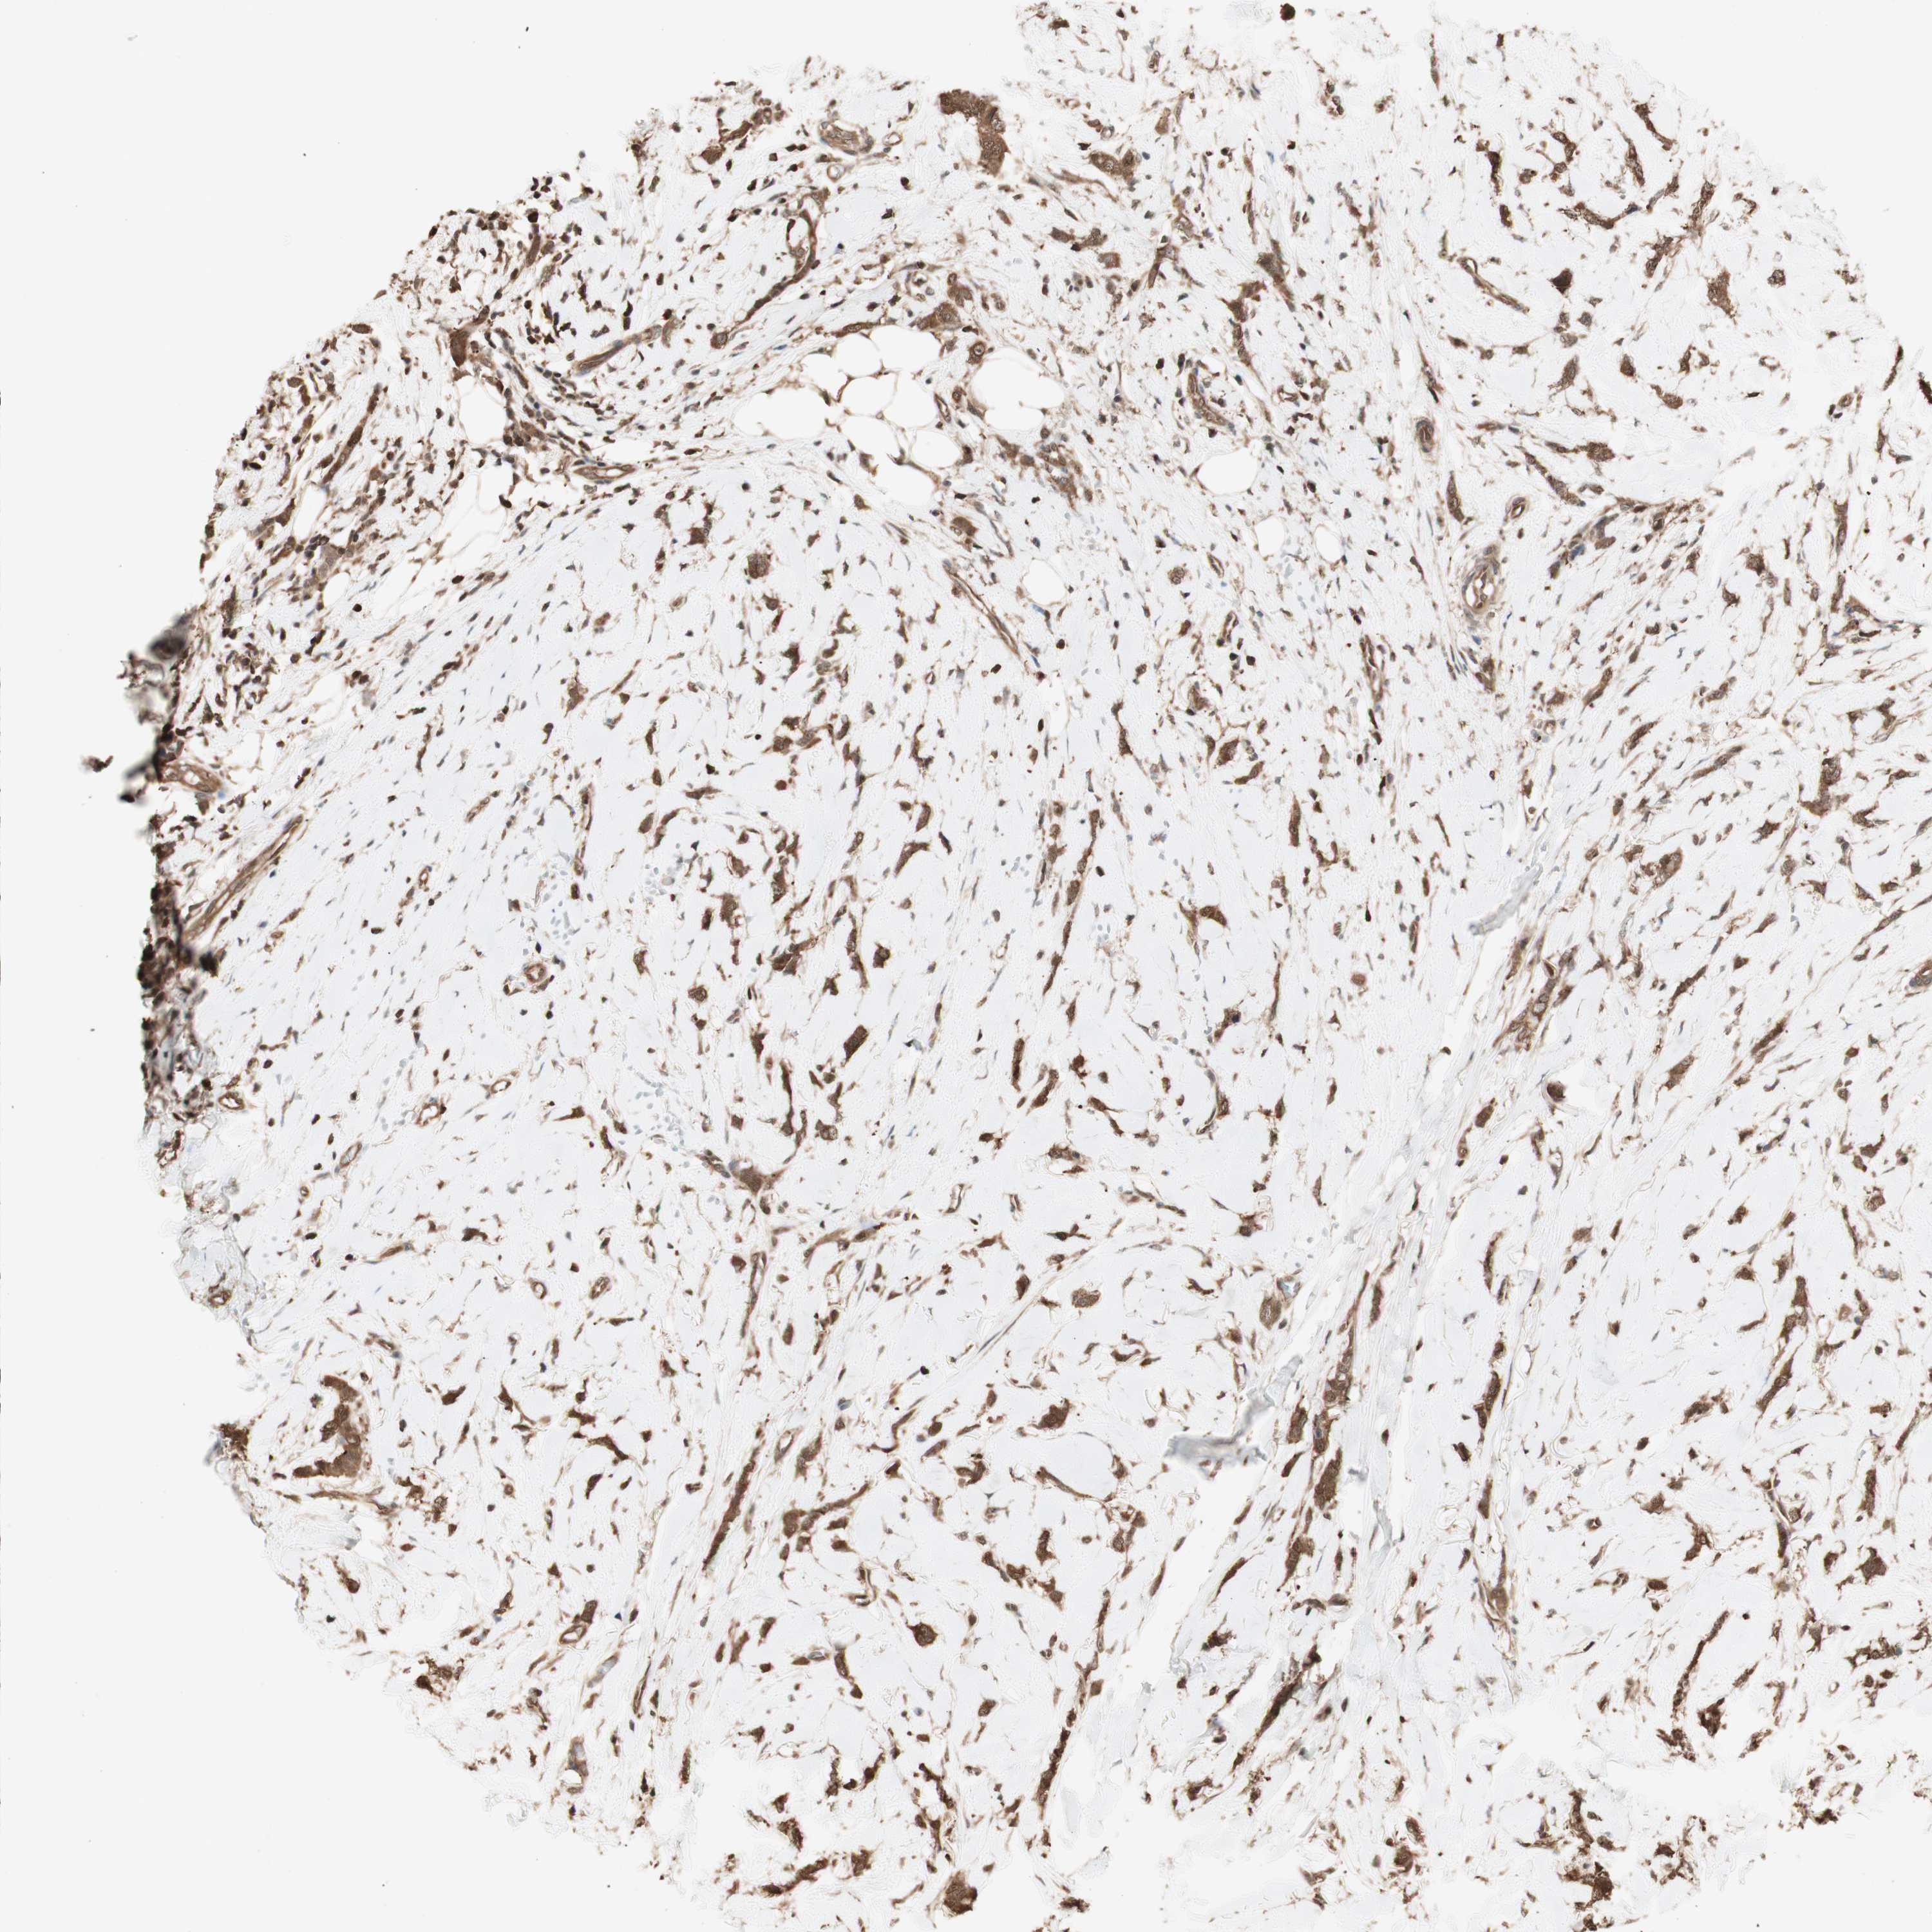

BRCA TCGA BRCA VALIDATION PROTEIN EXPRESSION

ANTIBODIES

AND

VALIDATION